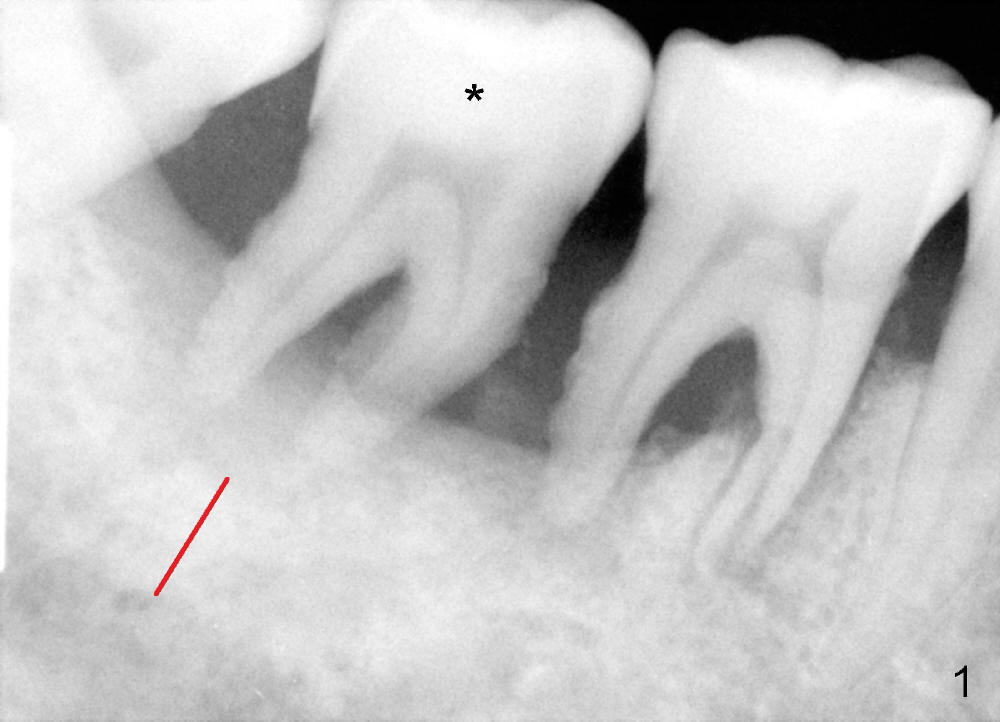

Mobility and pain associated with the lower right 2nd molar (Fig.1 *) are chief complaints from a 62-year-old man. Infiltration anesthesia allows for extraction and debridement of the socket, but not osteotomy with drills due to inability to achieve complete anesthesia. Because of limited bone height (Fig.1 red line), block anesthesia is not administered on purpose. Immediate implant is aborted; socket preservation is to be done. In short, pain control is a limiting factor for immediate implant. If pain is chief complaint prior to extraction, possibility of not performing immediate implant should be informed to the patient prior to the surgery. The patient should take antibiotic several days preop.